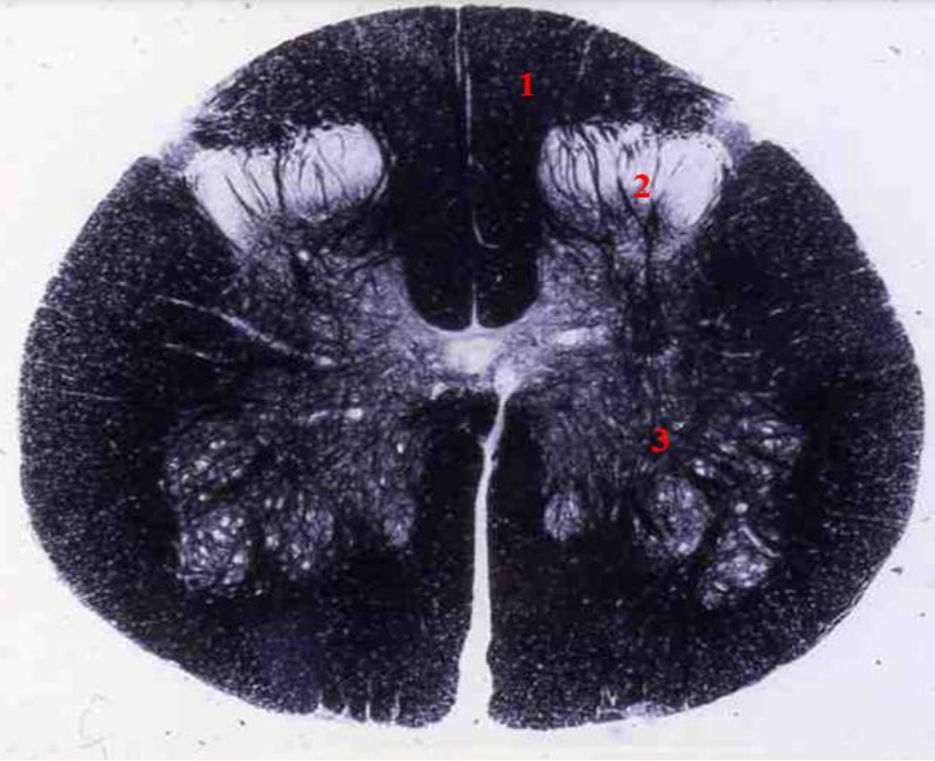

identify weigert

A

thoracic cord

- Fibre tracts are larger

- Grey matter is scanty as no limb plexuses

How well did you know this?

1

Not at all

2

3

4